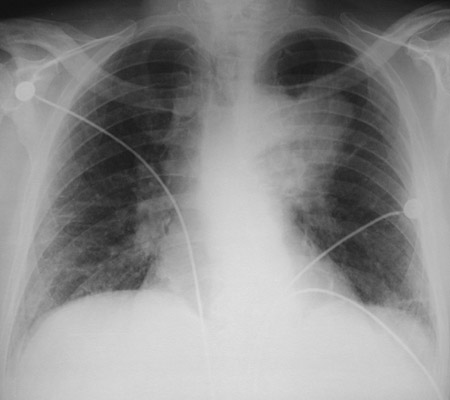

| The hilar mass seen here is a squamous cell carcinoma of the left upper lobe of lung. This is a form of bronchogenic carcinoma. Squamous cell carcinomas and small cell anaplastic carcinomas have the greatest association with smoking as a risk. Squamous cell carcinomas tend to form large, central masses because they often arise in larger airways. |